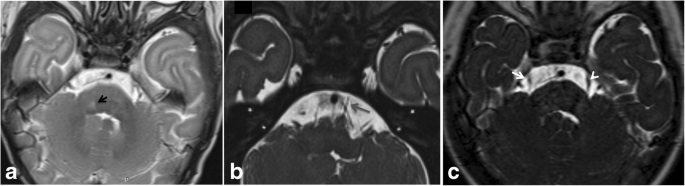

A male patient presented with horizontal diplopia and conjugate gaze palsy . Magnetic resonance imaging (MRI) revealed acute infarct in right facial colliculus which is an anatomical elevation on . . .

A lesion of the facial colliculus damages the facial nerve, producing a facial palsy affecting both the top and bottom of the face . This can sometimes be misdiagnosed as a Bell's palsy, which is also a peripheral VII nerve palsy but by definition is idiopathic .

Facial colliculus pathology causes LMN type of facial palsy, diplopia and horizontal conjugate gaze palsy . The abducens nerve innervates the ipsilateral lateral rectus muscle and directly controls abduction in the ipsilateral eye .

This rare condition, particularly when isolated, is caused by circumscribed lesions of the pontine tegmentum involving the abducens nucleus, the ipsilateral medial longitudinal fasciculus, and the adjacent facial colliculus . Its recognition is therefore of considerable diagnostic value .

When this lesion also affects the fascicle of the the ipsilateral facial nerve (CN VII) in the region of the facial colliculus as it wraps around the CN VI nucleus, it produces a lower motor neuron pattern of ipsilateral facial weakness . When this occurs, a one-and-a-half syndrome plus a 7th nerve palsy, it is termed an eight-and-a-half syndrome .

Facial colliculus syndrome usually results from a pontine glioma or a vascular accident • internal genu of CN VII • nucleus of CN VI underlie the facial colliculus .